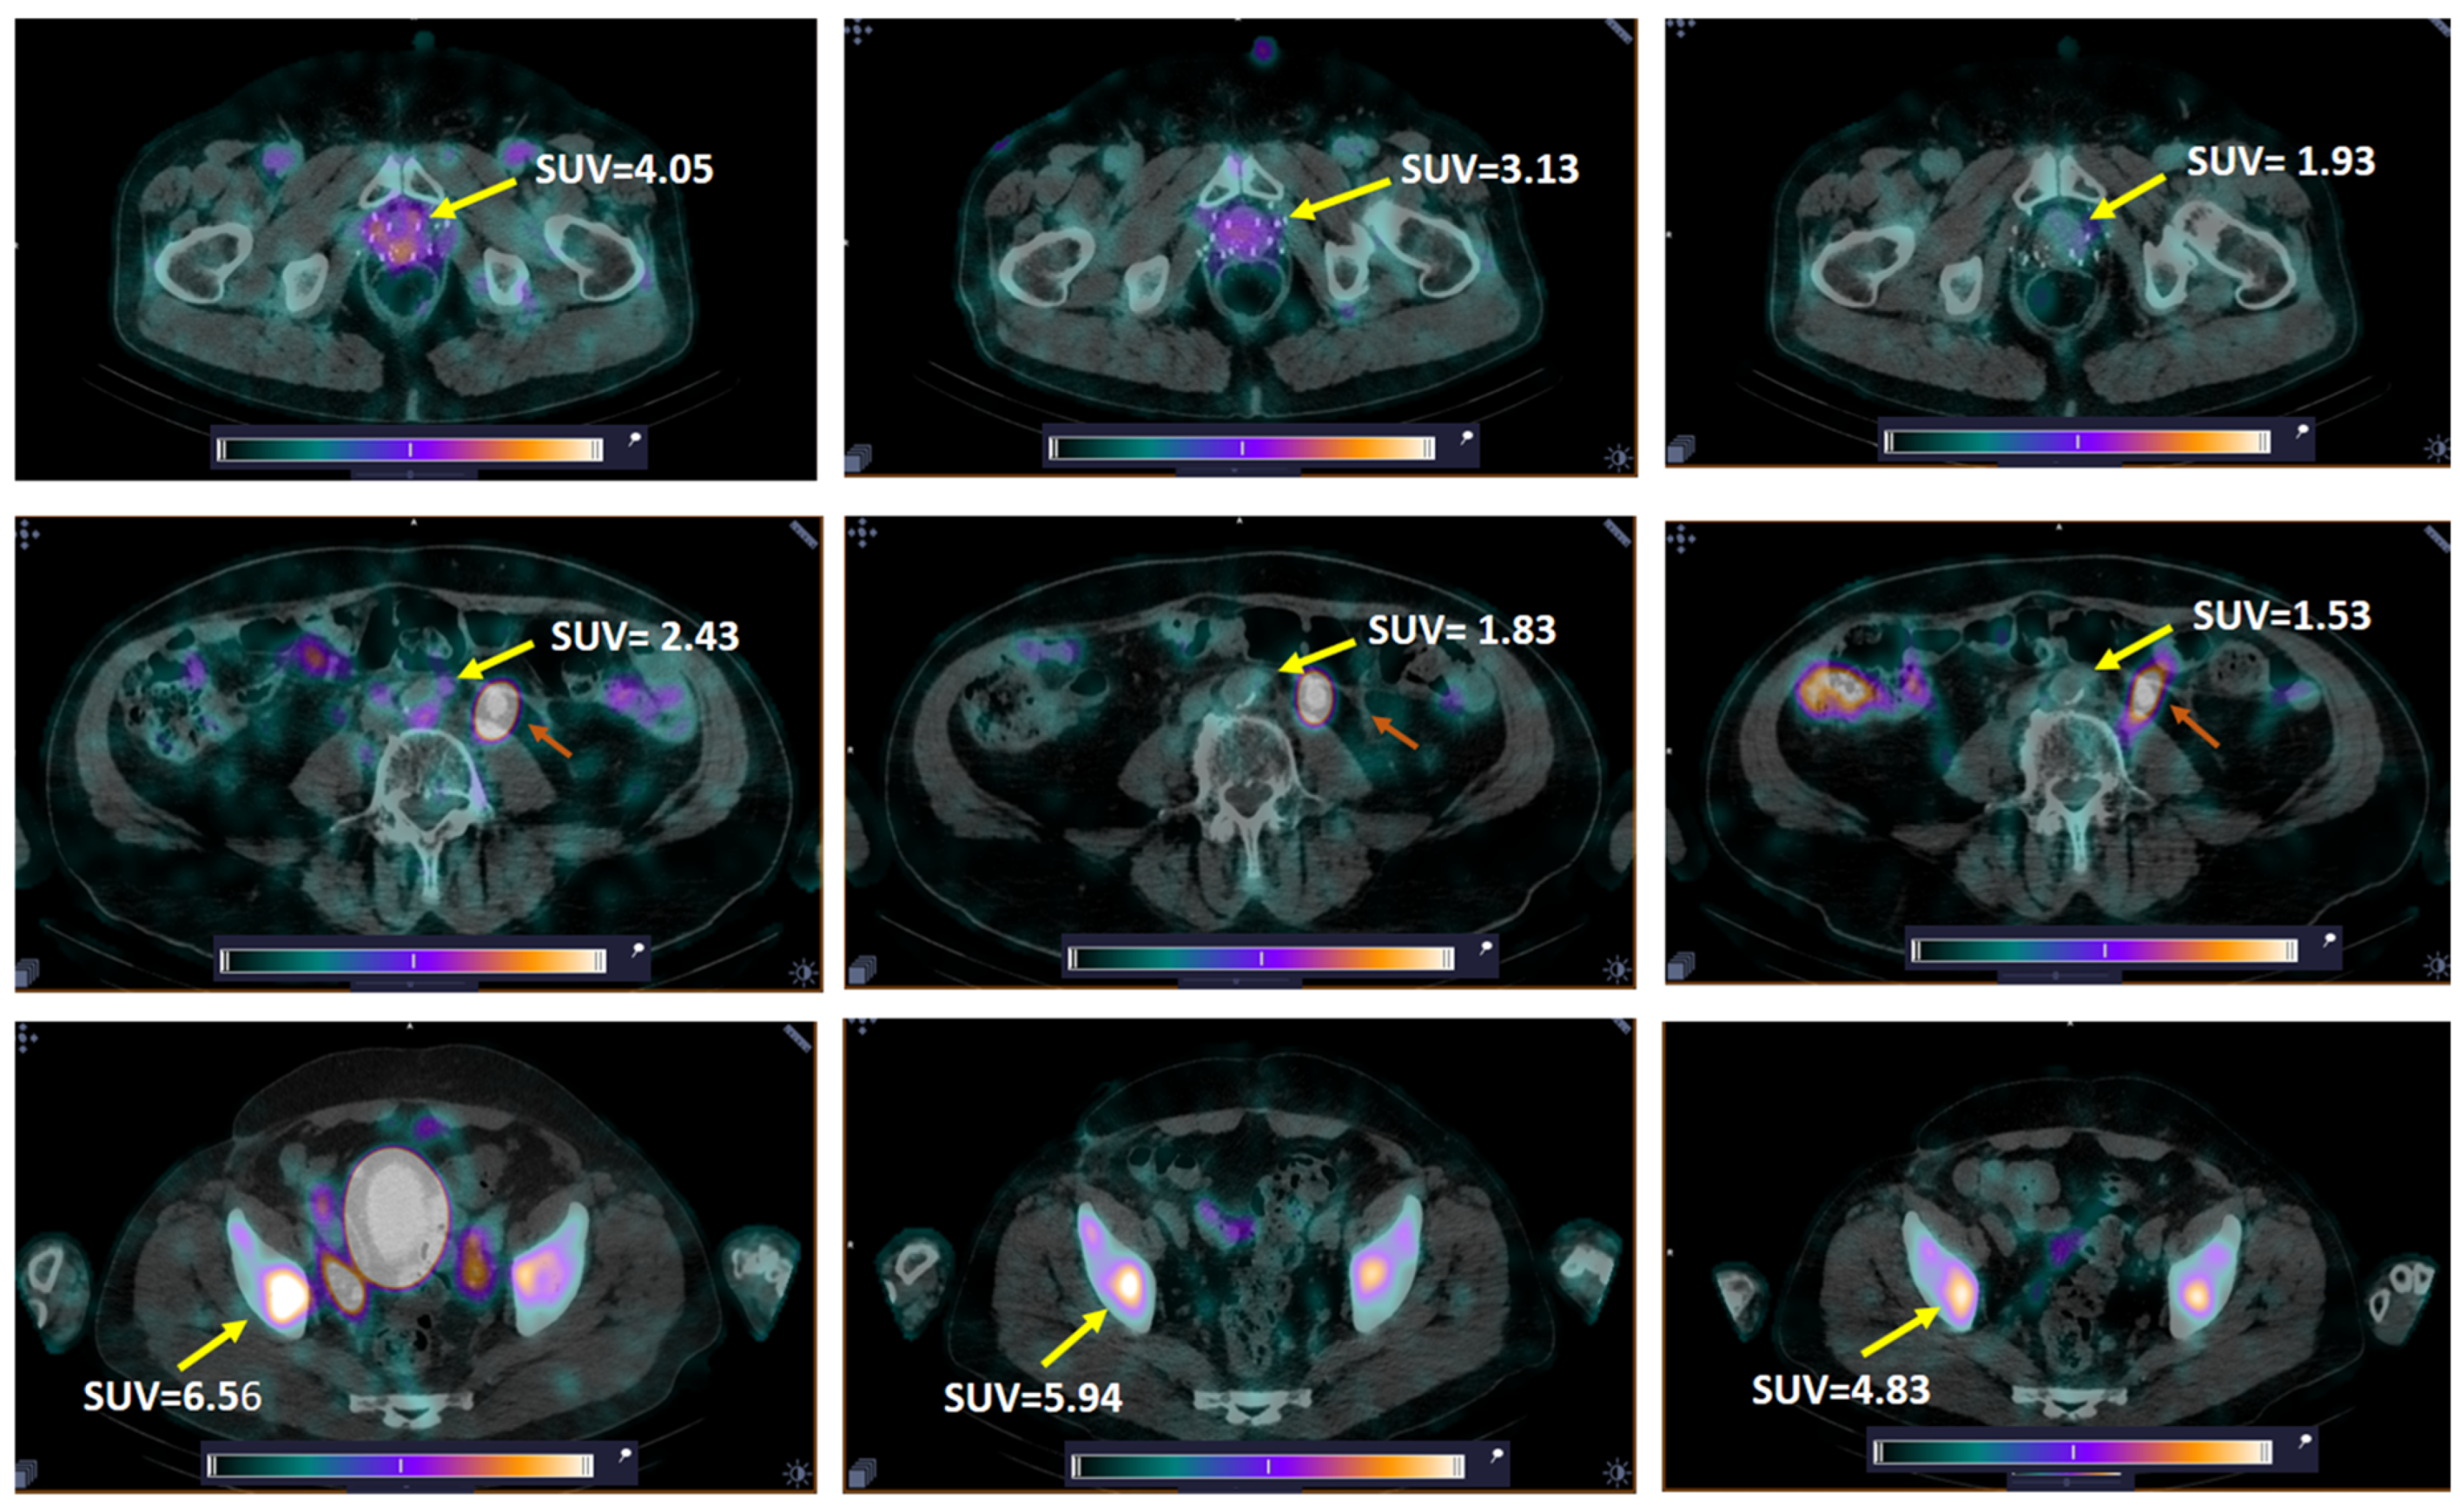

High-contrast images of tumors were obtained 2 h after administration of [99mTc]Tc-DB8 for all tested masses of peptide. Primary PCa lesions were visualized in 14 of 15 patients with primary tumors (93.3%; 1 patient underwent prostatectomy). The activity uptake in primary tumor, LNM, and BM lesions had a tendency to decrease with time (Figure 3c and Figure 5).

Figure 5. Decrease in tissue uptake (SUVmax) in primary tumor (upper panel, Patient 7), LNM (middle panel, Patient 13, paraaortic lymph node), and BM (bottom panel, Patient 10) with time. Yellow arrow—lesion; red arrow (middle panel)—dilated left ureter. A linear relative scale (normalized at the maximum activity in the image, SUVmax, from 0 to 5.0) is applied.

The activity uptake in primary lesions has a tendency to be higher after administration of [99mTc]Tc-DB8, corresponding to 120 µg peptide mass; however, the difference was statistically significant only at 4 h pi between uptakes after injections of 120 µg and 80 µg (Figure 3c). The activity uptake in primary lesions did not correlate with PSA concentrations in the blood, tumor size, or castration resistance. However, there was a tendency toward lower tumor uptake with increasing GS, determined by pathology examination (Figure 6). The image contrast (tumor-to-surrounding tissue SUVmean ratios) increased with time, a finding that was more pronounced for the group injected with the lowest peptide mass (Table 3).

LNMs were visualized in 2 out of 12 patients with known lesions (16.7%), and BMs in 2 out of 6 patients with known lesions (33.3%) (Figure 7). Additionally, activity uptake in BMs was visualized in two patients without known bone involvement according to CT. Patients with visualized LNMs and BMs were administered 80 or 120 µg of peptide. The SUVmax values for LNMs and surrounding tissues for individual patients were lower than for primary tumors in both groups injected with 80 and 120 µg of peptide, while for BMs, the group injected with 80 µg had a higher SUVmax than for primary tumors (Table 1). Nevertheless, the ratios for SUVmean in metastatic lesions to surrounding tissues were suitable for visualization: for LNM, 1.97–3.49 for 80 µg and 2.40–2.61 for 120 µg; for BM, 3.97–9.81 and 1.72–2.53, respectively.

All patients with visualized LNMs and BMs were injected with 80 or 120 µg of peptide. The activity uptake (SUVmax) in LNMs and BMs after injection of 120 and 80 µg at 2 h pi for all tested peptide doses did not differ significantly. The activity uptake in the lesions decreased with time; however, the imaging contrast increased due to faster clearance of activity from blood and healthy tissue (Figure 5 and Table 3). The comparison of activity uptake in primary tumors and uptake in the kidneys and pancreas (organs with the highest activity uptake in the abdomen) clearly demonstrated that activity uptake in healthy tissue decreased with an increase in the injected peptide mass, while uptake in primary PCa tumors did not differ significantly (Figure 3d–f). This could be tentatively attributed to differences in peptide delivery and uptake by the target cells, as well as subsequent activity release thereof between physiological tissues and tumors as a result of several distinct factors. Such factors are related to differences in GRPR expression patterns, anatomical location, and vascularization, as well as the overall biochemical milieu around the GRPR target area (especially in terms of local enzyme activity). It is not yet fully understood how these factors lead to the observed differences in uptake and retention between healthy tissues and tumors expressing the target. Nevertheless, similar effects have consistently been reported for other cancer-associated molecular targets, e.g., somatostatin receptors [47], PSMA [48], and human epidermal growth factor receptors type 1 [49] and type 2 [50]. In contrast, both activity uptake in the lesions and tumor-to-background ratios were significantly higher for the intermediate peptide dose of 80 µg in female patients with BCa [31]. It might be speculated that this difference could be related to a difference in GRPR expression between PCa and BCa, on the one hand, and, on the other, to gender. Thus, the use of a higher peptide dose should enhance high-contrast imaging in PCa. Imaging at 2–4 h pi of 80–120 µg of [99mTc]Tc-DB8 could be recommended for future clinical studies based on activity uptake in lesions and in healthy tissues observed in this study.